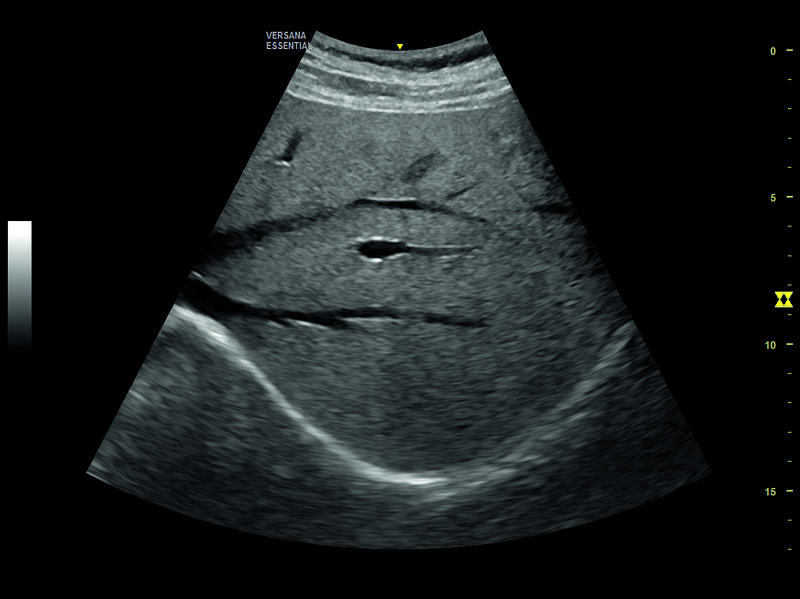

GE Versana Essential

Tecnología de confianza GE y una excelente calidad de imagen para asegurar su diagnóstico con precisión. Versana Essential, pone a su disposición una amplia gama de sondas y numerosas funciones innovadoras para una rápida optimización de la imagen en los exámenes de rutina veterinarios

Versana Balance le ofrece una calidad de imagen excelente, alineada con las mejores en su clase. Las imágenes brindan alta resolución espacial y de contraste para ayudarle a visualizar las estructuras anatómicas y las funciones fisiológicas, con la misma precisión de los modelos superiores.